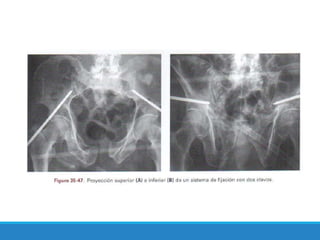

Este documento describe las fracturas de pelvis, incluyendo su etiología, mecanismos, clasificación y tratamientos. Las fracturas de pelvis se clasifican según el sistema de clasificación de Tile, que categoriza las fracturas como Tipo A, B o C dependiendo de su estabilidad y ubicación. El tratamiento depende de la clasificación Tile, con reposo para el Tipo A, estabilización del anillo anterior para el Tipo B, y estabilización anterior y posterior para el Tipo C.